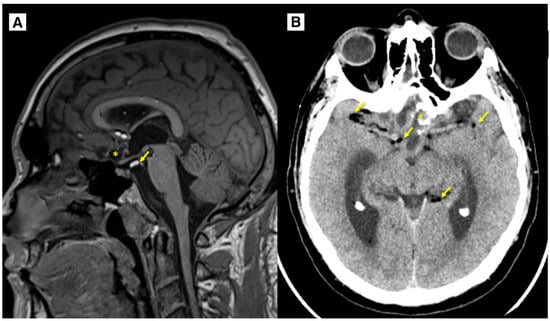

2.2. Imaging Findings